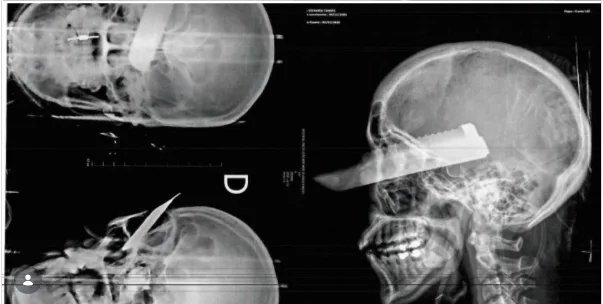

De acordo com a Polícia Civil, a tentativa de crime ocorreu nas primeiras horas do dia. Durante uma discussão, o suspeito teria agredido a vítima e, no momento em que ela tentou fugir, desferiu um golpe de faca no rosto, atingindo o olho direito da mulher. A polícia aponta que a ação teve clara intenção de matar.